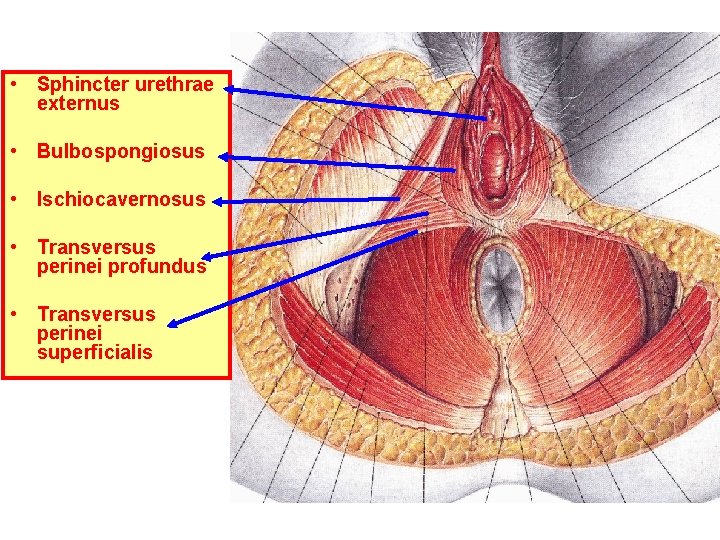

• Sphincter urethrae externus • Bulbospongiosus • Ischiocavernosus • Transversus perinei profundus • Transversus perinei superficialis